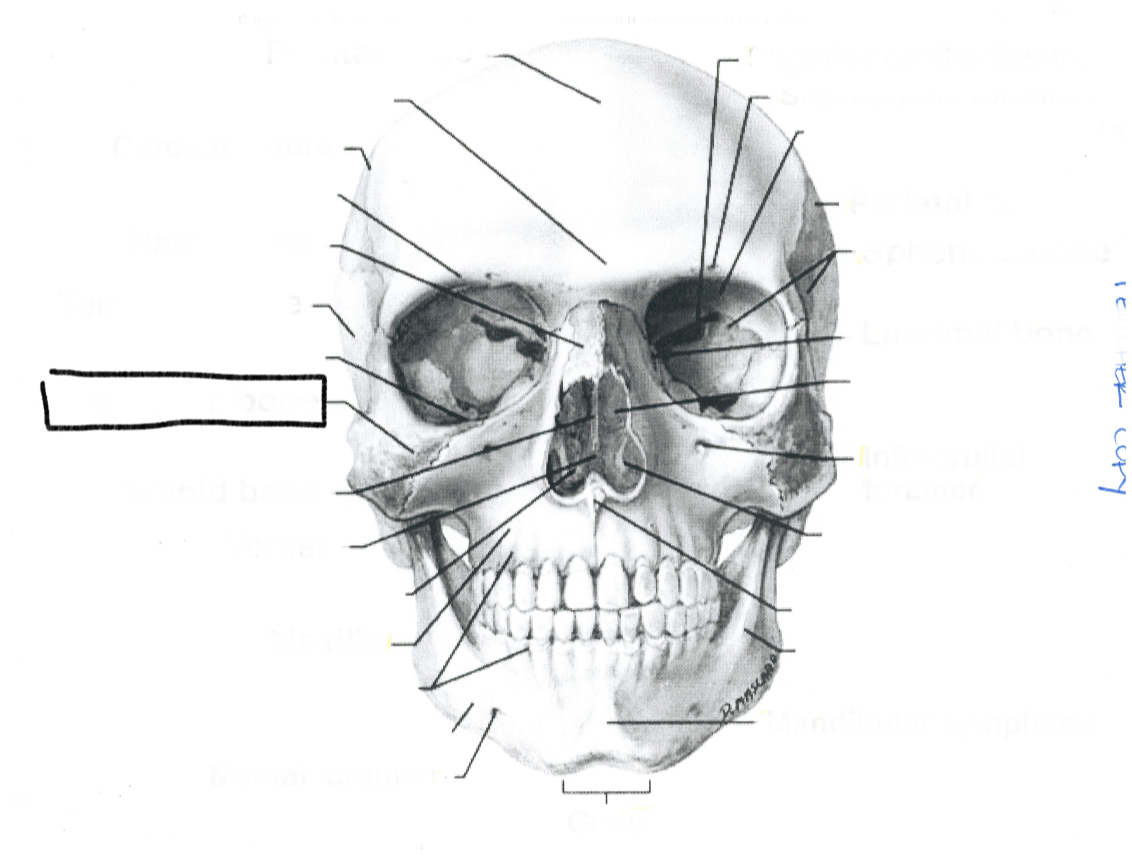

What is this?

Lacrimal bone

What is this?

Sphenoid bone

What is this?

Parietal bone

What is this?

Infraorbital foremen

What is this?

Supraorbital foramen

What is this?

Superior orbital fissure

What is this?

Mandibular symphysis

What is this?

Genu

What is this?

Mental foramen

What is this?

Maxilla

What is this?

Ethmoid bone

What is this?

Zygomatic bone

What is this?

Temporal bone

What is this?

Nasal bone

What is this?

Coronal suture

What is this?

Frontal bone